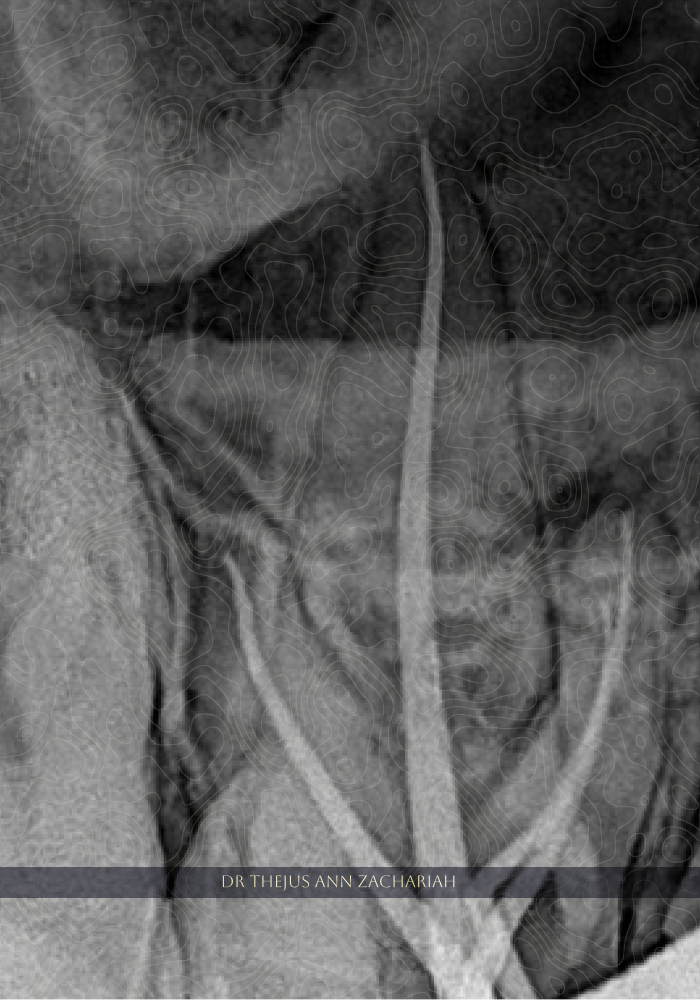

Post-Operative X Ray

alt text